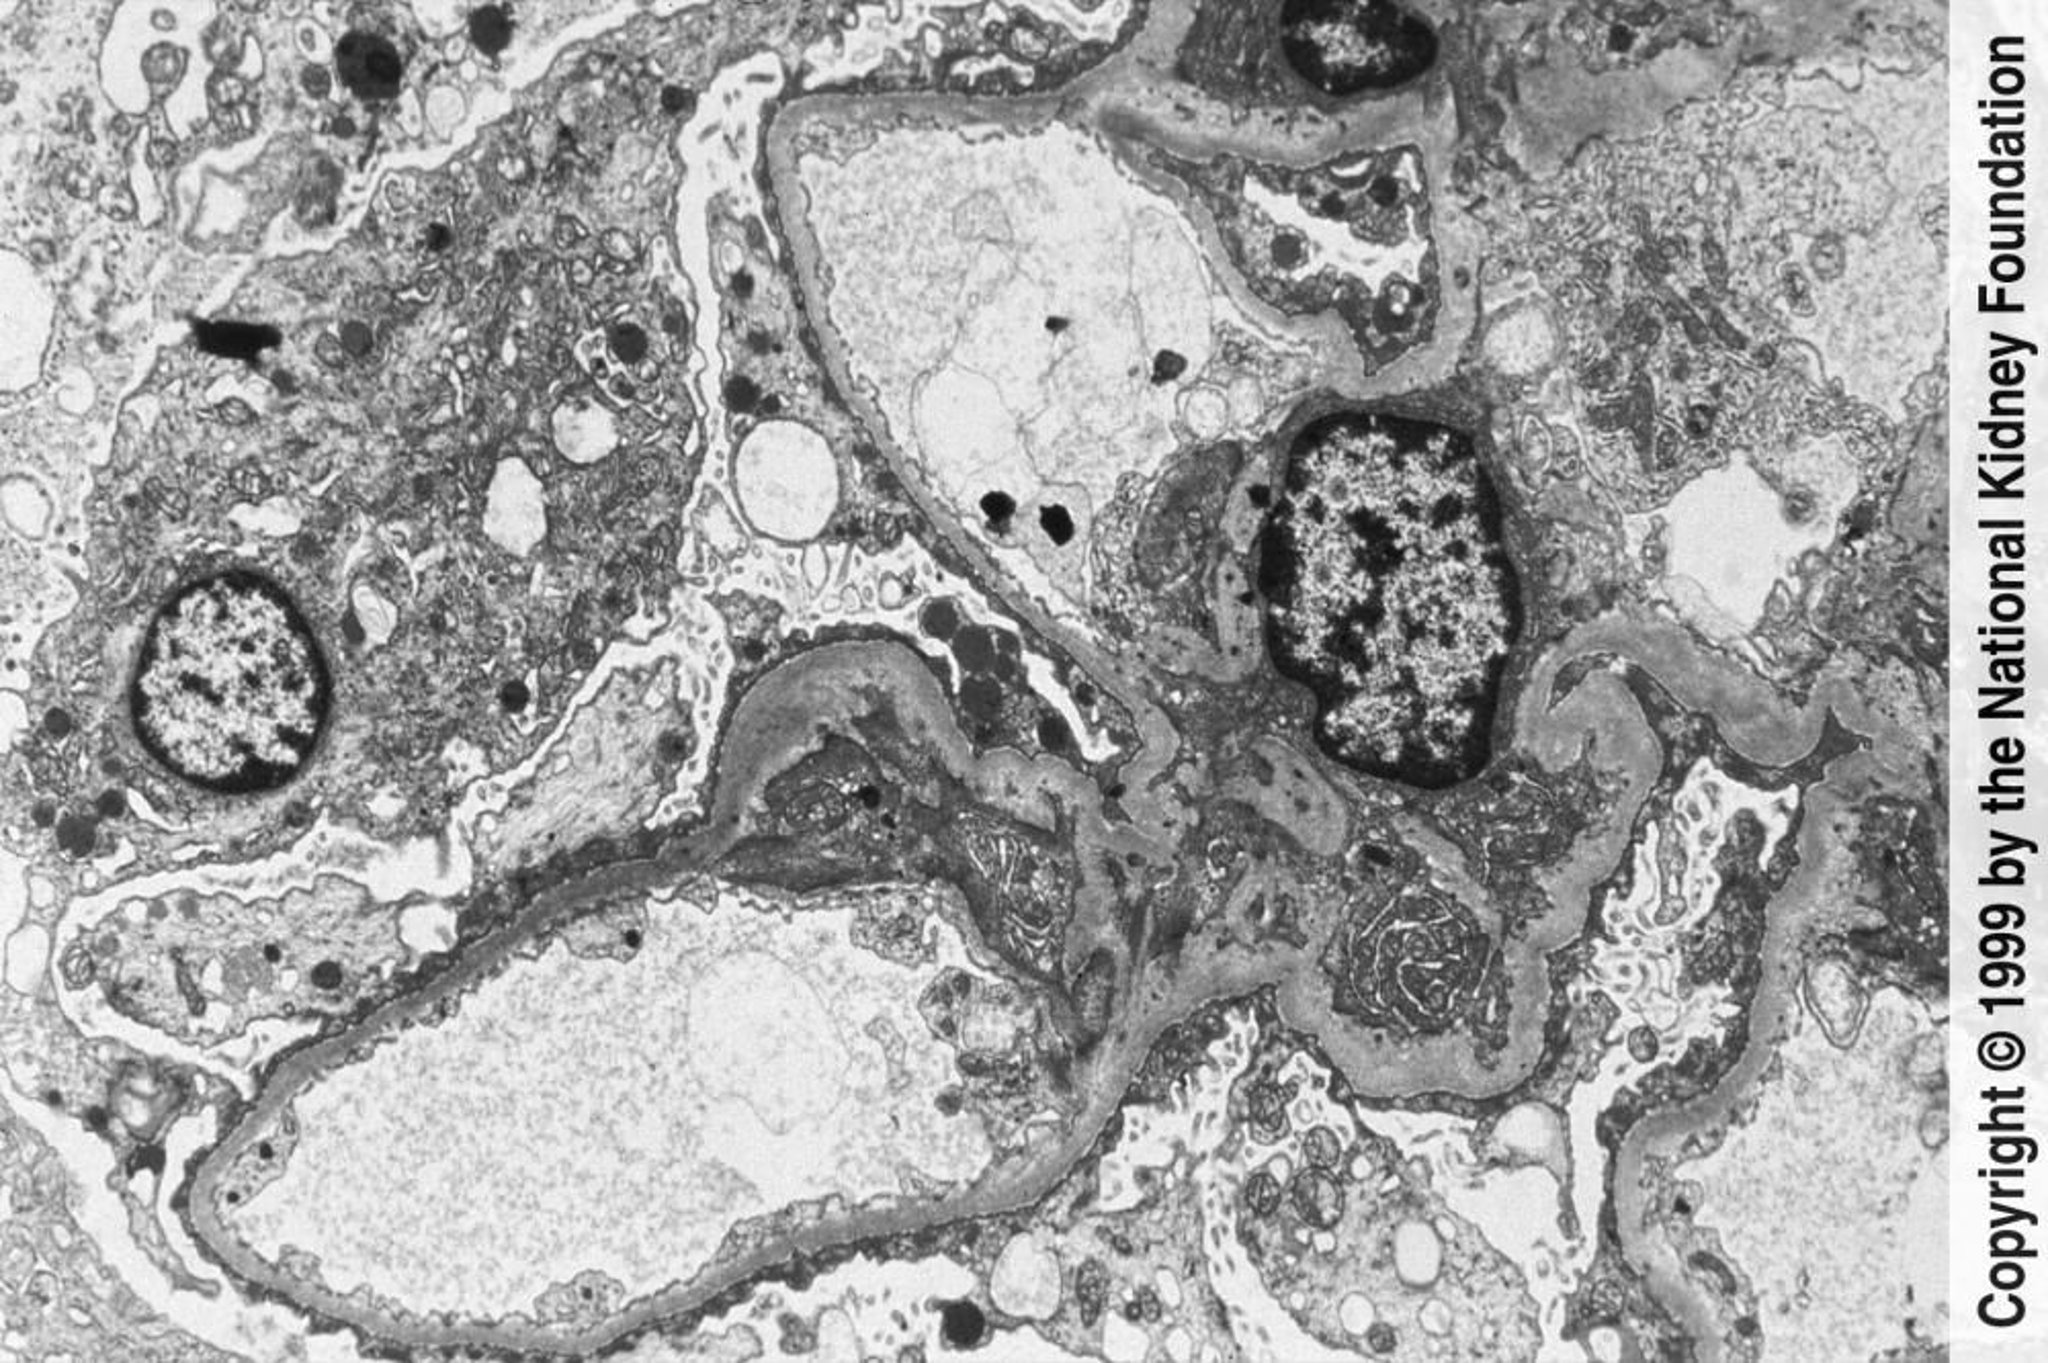

Fokal-segmentale Glomerulosklerose (Abstumpfung und Verkleinerung der Podozyten)

In der Transmissionselektronenmikroskopie (×3000) ist eine weitgehende Abstumpfung und Auslöschung der Podozyten zu erkennen.